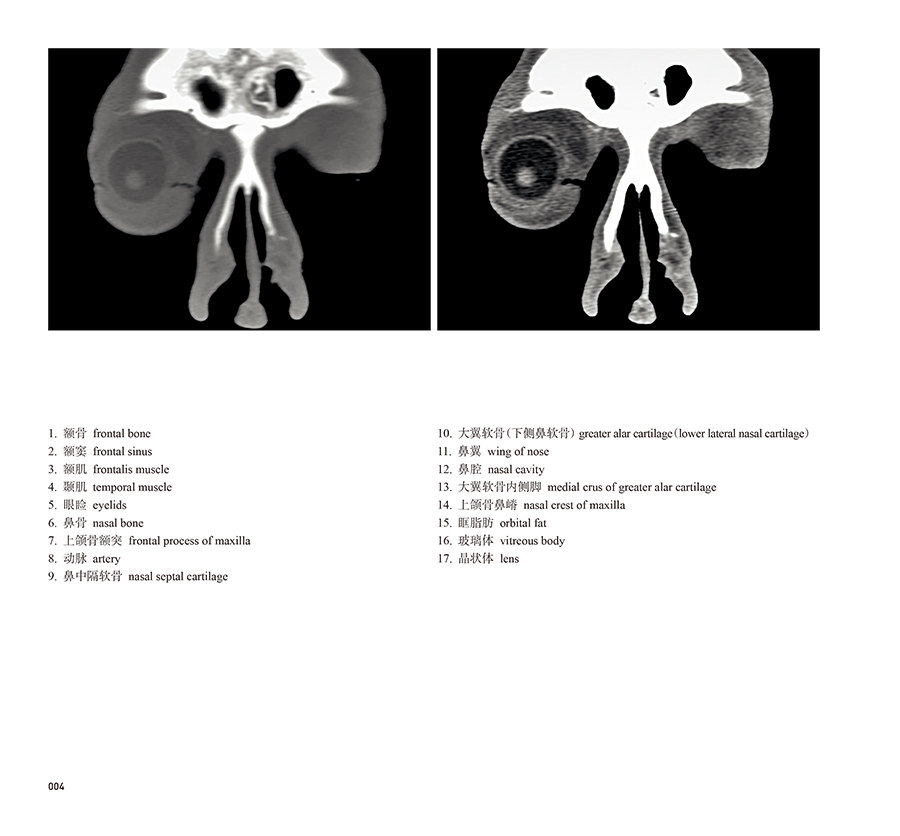

本书从数据集每隔1.2mm选取一幅图像,截取眼、耳、鼻及毗邻颅底的局部区域图像,共112幅图像。同时配以相应部位的CT图像对照。本书特色是断层解剖图利用数字图像处理技术优势,放大并清晰展示眼、耳、鼻及毗邻颅底断面的局部区域结构,组织色泽真实,甚至能够清晰显示肌肉纹理、筋膜纹路等细节结构,图像质量高于美国《人体断层解剖学彩色图谱》(引进版)类似图谱图像质量。对眼科、耳鼻咽喉科和神经内外科医生理解相关解剖结构有较大帮助。